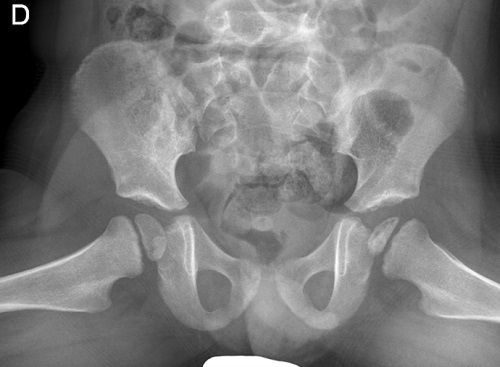

Figura 1. Cadera AP. Discreto colapso epifasio en cadera izquierda

Figura 1. Cadera AP. Discreto colapso epifasio en cadera izquierda.

Presentamos un paciente varón de 2 años con dolor en cadera izquierda y cojera de 2-3 días de evolución que consulta a su pediatra. No presentaba ningún antecedente de traumatismo o sobreesfuerzo los días previos. Se orienta el caso como una sinovitis transitoria de cadera y se instaura tratamiento con antiinflamatorios no esteroideos (AINE) y reposo, con mejoría a los 3 días. En el mes posterior, presenta dos nuevos episodios de cojera izquierda, que se trataron con AINE con mejoría en 3-4 días. Se realizó una radiografía de cadera sin alteraciones, manteniéndose conducta expectante. Reconsultan tras cuarto episodio de cojera izquierda, este de 5 días de duración, que no ha mejorado pese al tratamiento antiinflamatorio. Dada la evolución tórpida, se completa estudio con analítica sanguínea sin elevación de reactantes de fase aguda y radiografía (Rx) y ecografía de cadera. En la Rx se aprecia el signo de la cáscara de huevo característica de la enfermedad de Perthes (Figs. 1 y 2), y en la ecografía, un mínimo derrame articular. Se consulta con Traumatología, que indica evitar apoyo de la extremidad afectada y reposo, e inicia controles en sus consultas. Buena evolución posterior con recuperación funcional progresiva.